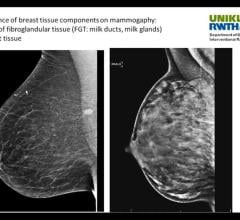

Professor Christiane Kuhl, M.D., director of radiology, University Hospital Aachen, Germany, explains how breast ...

Professor Christiane Kuhl, M.D., director of radiology, University Hospital Aachen, Germany, explains what it means to ...